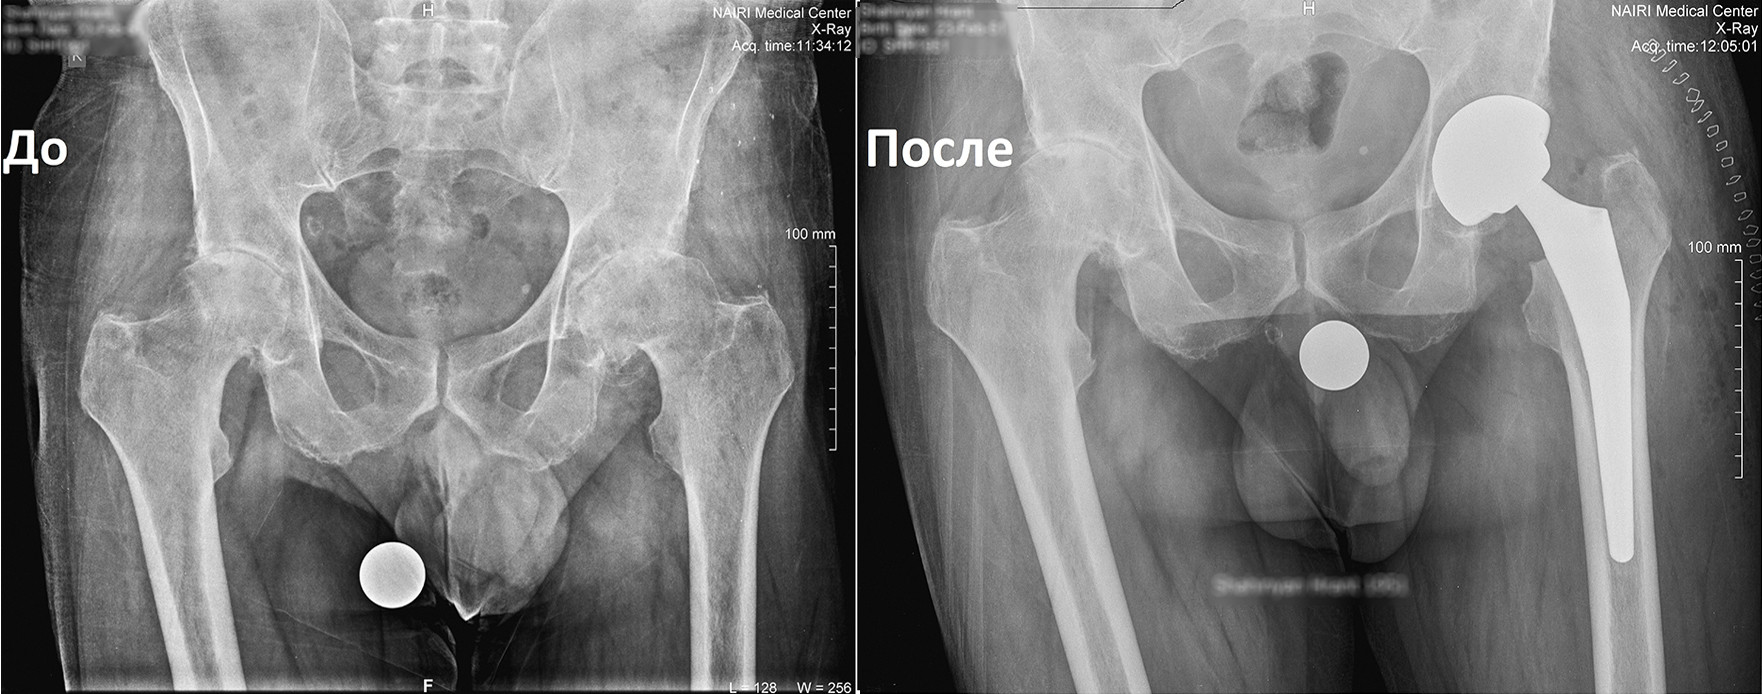

Կլինիկական դեպք. երկկողմանի անգիլիզացնող կոքսարթրոզ

«Նաիրի» բժշկական կենտրոն էր դիմել 1951 թ. ծնված տղամարդ՝ երկկողմանի անգիլիզացնող կոքսարթրոզով, առաջին աստիճանի ճարպակալումով: Պացիենտը գանգատվում էր մշտական ցավերից, շարժումների խիստ սահմանափակումից, քայլելու դժվարությունից՝ անգամ հենակների oգնությամբ:

Որոշում կայացվեց իրականացնել փուլային երկու վիրահատություն: Առաջինը վիրահատվեց ձախ ոտքը, քանի որ այդ վերջույթում ձևախախտումն առավել արտահայտված էր:

Երկու ամիս անց, երբ պացիենտը սկսեց քայլել առանց հենակների, վիրահատվեց նաև աջ ոտքը:

Երկրորդ վիրահատությունից 6 շաբաթ անց պացիենտը ցավեր չունի և քայլում է առանց հենակների, ապրում լիարժեք կյանքով: